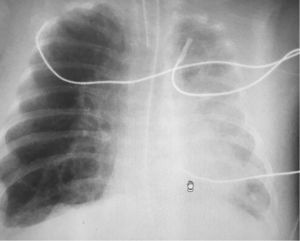

A 4-month-old, ex-premature (24 weeks of pregnancy) patient with severe bronchopulmonary dysplasia on mechanical ventilation (pressure control mode with PIP 25cmH2O, PEEP 5.5cmH2O, respiratory frequency 35rpm and FiO2 30%). On the reported day, the patient required FiO2 of up to 50%, and the chest X-rays (Fig. 1) showed intense hyperinsufflation of the right hemithorax and the absence of the lung sliding sign at pulmonary ultrasound (Fig. 2). In view of the evolution of patients with bronchopulmonary dysplasia towards dynamic compression of the distal airway, we decided to progressively increase PEEP, without ultrasound improvement until PEEP 10cmH2O was reached; at this point pleural sliding was seen to reappear (Fig. 3) and the chest X-rays showed partial resolution of the overdistension (Fig. 4).